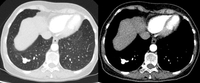

Computed tomography (CT) showing examples of malignant perifissural nodules. Note the spiculated edge of the nodules and the evident retraction of the adjacent fissure. Both resection tissue analyses confirmed adenocarcinoma of lung

From the collection of Dr George Tsaknis, MD, PhD, FRCP(London), MRQA, MAcadMEd, PGCert; used with permission